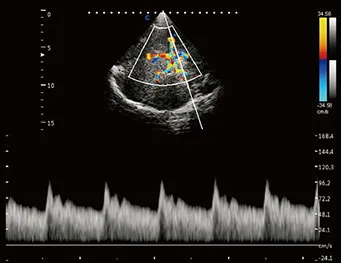

Zoom C HD

Haga zoom en la información de color, siga siendo la alta resolución.

Importante para la detección de información de sangre de vasos pequeños, especialmente para el diagnóstico de corazón fetal.